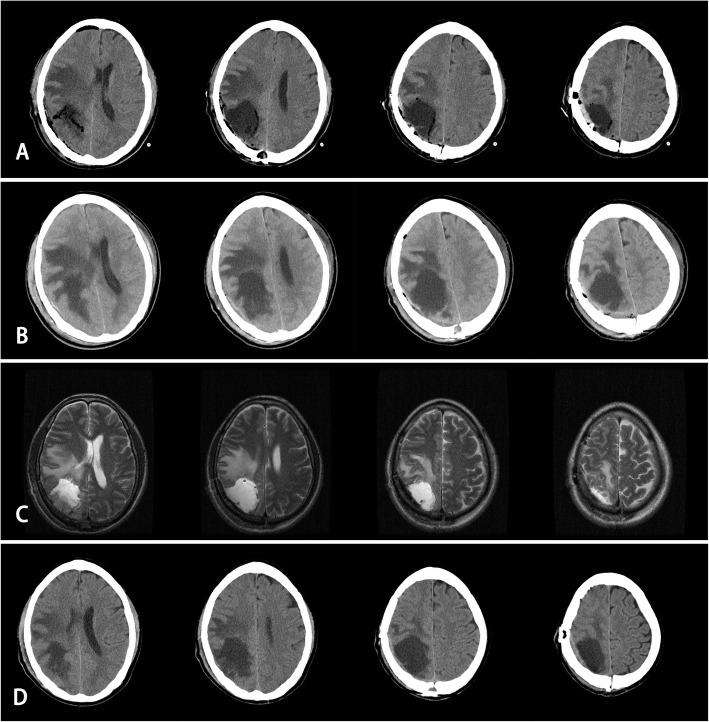

In neurosurgery, the necessity of having a drainage tube is controversial. Subgaleal fluid collection (SFC) often occurs, especially in a craniotomy near the "parietal site".This study aimed to reassess the benefit of using a prophylactic epidural drainage (ED) and non-watertight dura suture in a craniotomy near the parietal site.

METHODS

A retrospective review was conducted on 63 consecutive patients who underwent a craniotomy near the parietal site. The patients were divided into two groups according to different period. The deal group received ED and a non-watertight dura suture (drain group, DG), the control group that did not (non-drain group, NDG). Complications and patient recovery were evaluated and analysed.

Three patients (11.5%, 26) in DG and 20 patients (54.1%, 37) in NDG presented with SFC ( < 0.05). One patient (3.8%) in DG and three patients (8.1%) in NDG presented with subdural tensile hydrops (STH) ( > 0.05). Six developed an infection in NDG (four intracranial infections, one abscess, one pulmonary infection), while none in DG ( > 0.05) developed infection. Three (11.5%) cases in DG and one (2.7%) case in NDG had muscle strength that improved postoperatively ( > 0.05). Fifteen (57.7%) in DG and 14 (37.8%) in NDG had epileptic seizures less frequently postoperatively ( < 0.05). The average temperature (37.4 °C vs 37.6 °C, > 0.05), the maximum temperature (37.9 °C vs 38.1 °C, > 0.05) on 3 PODs, the postoperative hospital stay day (7.5 days vs 8.0 days, > 0.05), and the postoperative medicine fee (¥29762.0 vs ¥28321.0, > 0.05) were analysed.

In patients who undergo a craniotomy near the parietal site, the prophylactic use of ED and a non-watertight dura suture helps reduce SFC, infection, and control epilepsy.